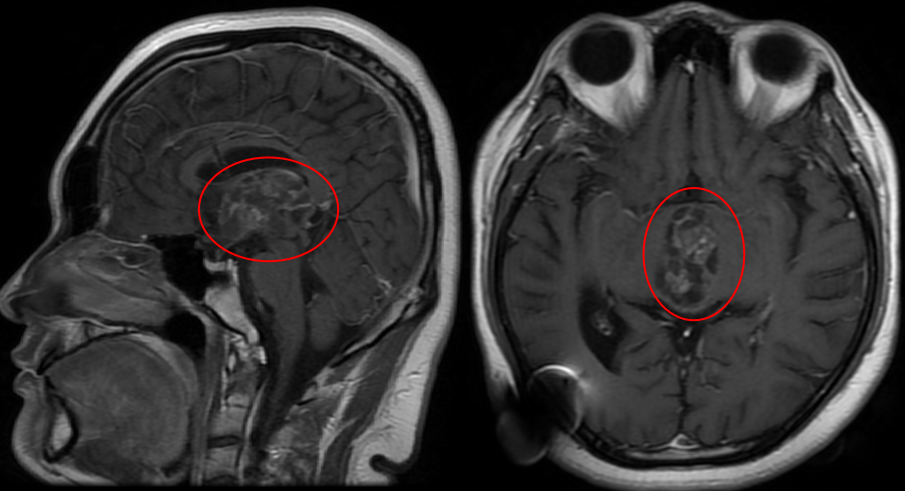

随后他们尝试中医药治疗,可惜效果不佳。现实终究严峻:飞宇在成长,肿瘤也在增大。眼科检查出现复视现象,视力显著下降、视野缺损——MRI检查显示,40毫米的巨大肿瘤已占据第三脑室,正悄然侵蚀少年的未来。

术前MRI检查结果

"今年复查显示肿瘤继续增大,不能再等待。"这次,他们毫无犹豫。恰逢巴特朗菲教授来华交流,从7月31日复查到8月12日手术,仅间隔十余天。"实际上我们从开始就认定要选择最佳治疗方案。这是脑部手术,我们必须给他最好的医疗条件。"

这个40×25×31毫米的巨大肿瘤完全占据第三脑室,并从室间孔向下压迫中脑结构,使手术面临多重挑战。首先,手术路径深长且狭窄,需要在切开胼胝体、分离脉络膜裂后,在有限操作空间内精准切除肿瘤,对手术稳定性要求极高。其次,肿瘤导致关键脉络膜裂发生扭曲、变薄,与周围深部静脉系统和丘脑粘连紧密,分离过程中极易引发出血或梗死。再者,肿瘤本身血供丰富且质地坚韧类似橡皮,与第三脑室壁、丘脑、深部血管紧密粘连,只能分块切除或借助超声吸引器(CUSA),强行牵拉容易导致出血或损伤周围组织。